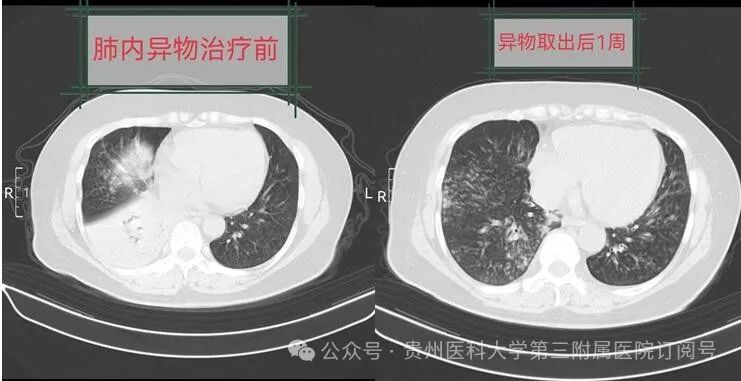

取出鱼骨头后,韦阿姨相关症状明显好转。1周后,复查胸部CT,白肺逐渐吸收好转,现她已康复出院。